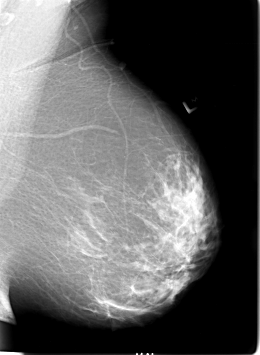

B_3020_1.RIGHT_MLO

B_3020_1.LEFT_MLO

B_3020_1.RIGHT_CC

B_3020_1.LEFT_CC

LEFT_MLO LINES 5672 PIXELS_PER_LINE 4160 BITS_PER_PIXEL 12 RESOLUTION 50 NON_OVERLAY

RIGHT_MLO LINES 5680 PIXELS_PER_LINE 4120 BITS_PER_PIXEL 12 RESOLUTION 50 OVERLAY